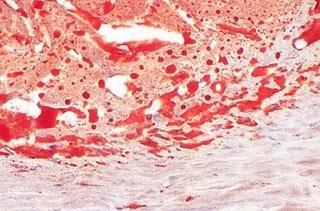

Tincion de una placa en un Ateroma con sudan IV

Otra forma de preparar el Sudán IV es pesando 1 g de Sudán IV, disuelva en 100 mL de etanol 95%, caliente hasta ebullición. Después agregue 40 mL de glicerina a 60 mL de la solución. Para teñir en cualquiera de los dos casos, corte secciones muy delgadas del material y agregue el colorante deje actuar por 20 minutos y luego caliente suavemente.

Para la fijación previa del tejido el mejor fijador es el formol, que, si bien fija totalmente las grasas neutras, actúa de manera variable sobre le resto de las estructuras lipídicas (colesterol y derivados, fosfolípidos, esfingolípidos...). El formol es aún mejor fijador de grasas si se emplea como formol-cálcico (formol al 10% y cloruro cálcico al 1%). De esta manera los iones de calcio estabilizan los lípidos y el formol los fija más eficazmente.